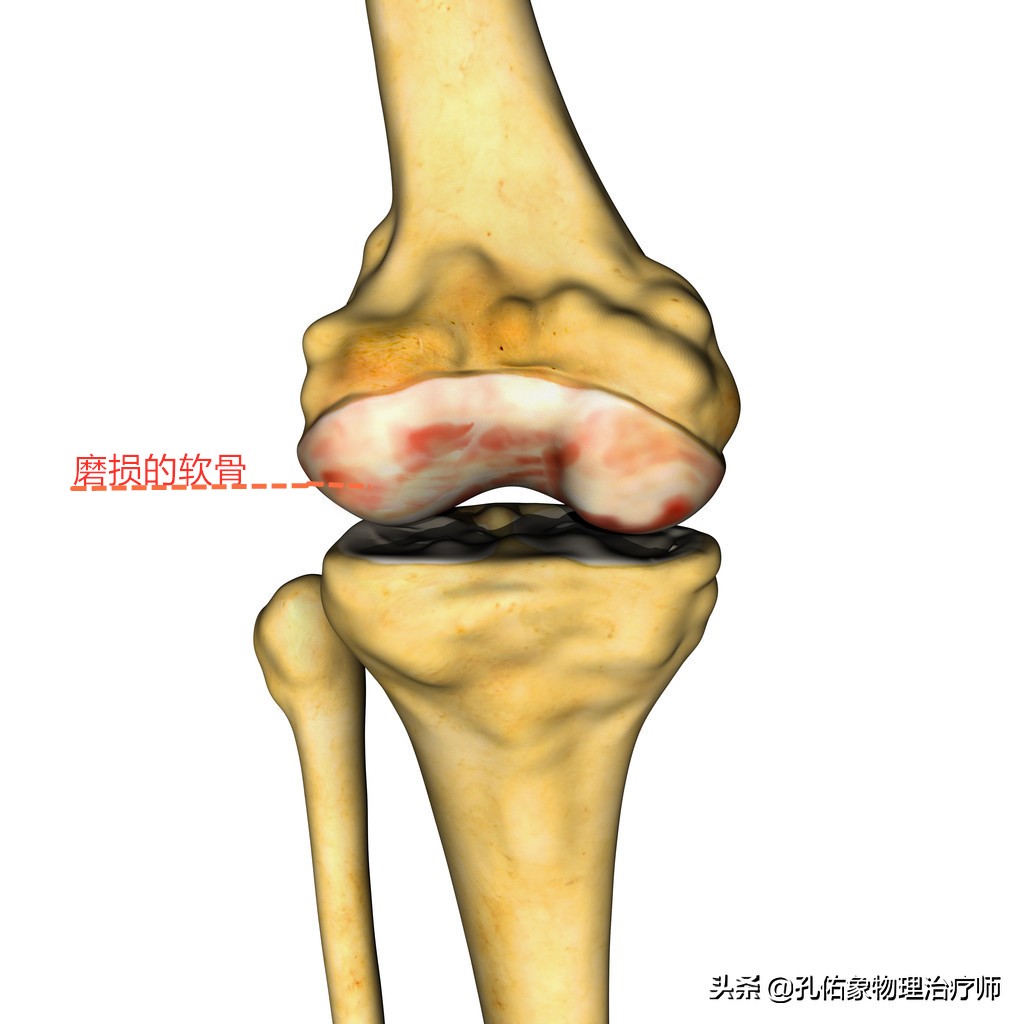

在正常人体膝关节中,大腿骨和小腿骨及膝盖骨的连接处关节面,还有一种很重要的结构,如下图所示的灰白色物质,就是软骨。

软骨

但凡你过度使用膝关节,或是腿型及姿势的异常,使膝关节不恰当的受力,就会导致关节面上的软骨发生磨损,软骨下面的骨质就会在膝关节活动屈伸小腿时相互接触摩擦而导致疼痛,从而影响膝关节内部的滑膜增生,导致关节的积液肿胀。这种问题就是我今天要着重介绍的髌骨软骨软化,不知你听说过没?了解过没?

听上去这个名字很新鲜,若是从字面去理解就是软骨出现了问题,出现了软化;其实就是前面介绍的,软骨受到磨损。软骨一旦受到磨损之后,就会使软骨的组成物质(胶原蛋白)随之减少,出现局部的疏松,类似于水土流失后的土壤一样,很容易在应力下出现问题。如下图所示:

磨损的软骨